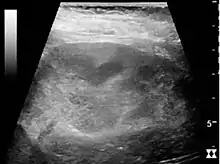

In medical imaging, the acute changes in the kidney are often examined with renal ultrasonography as the first-line modality, where CT scan and magnetic resonance imaging (MRI) are used for the follow-up examinations and when US fails to demonstrate abnormalities. In evaluation of the acute changes in the kidney, the echogenicity of the renal structures, the delineation of the kidney, the renal vascularity, kidney size and focal abnormalities are observed.[16] CT is preferred in renal traumas, but US is used for follow-up, especially in the patients suspected for the formation of urinomas. A CT scan of the abdomen will also demonstrate bladder distension or hydronephrosis.

Renal ultrasonograph in renal trauma with laceration of the lower pole and subcapsular fluid collection below the kidney.[16]